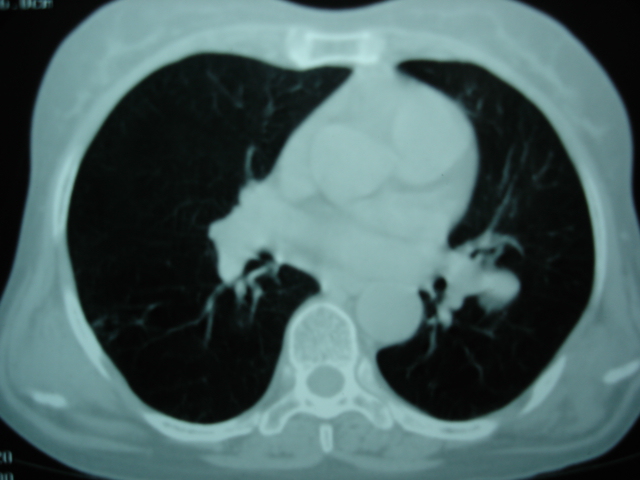

以下是引用卜一在2009-9-7 19:51:00的发言:[br][br] 1 左侧胸内甲状腺占位-多考虑甲状腺腺瘤! 2、左肺门占位-建议增强扫描以便明确性质。 3 慢支并感染! [br]

以下是引用shibing在2009-9-7 20:40:00的发言:[br]左侧胸内甲状腺占位-多考虑甲状腺腺瘤! 2、左肺门占位-建议增强扫描以便明确性质。 3 慢支并感染! [br]